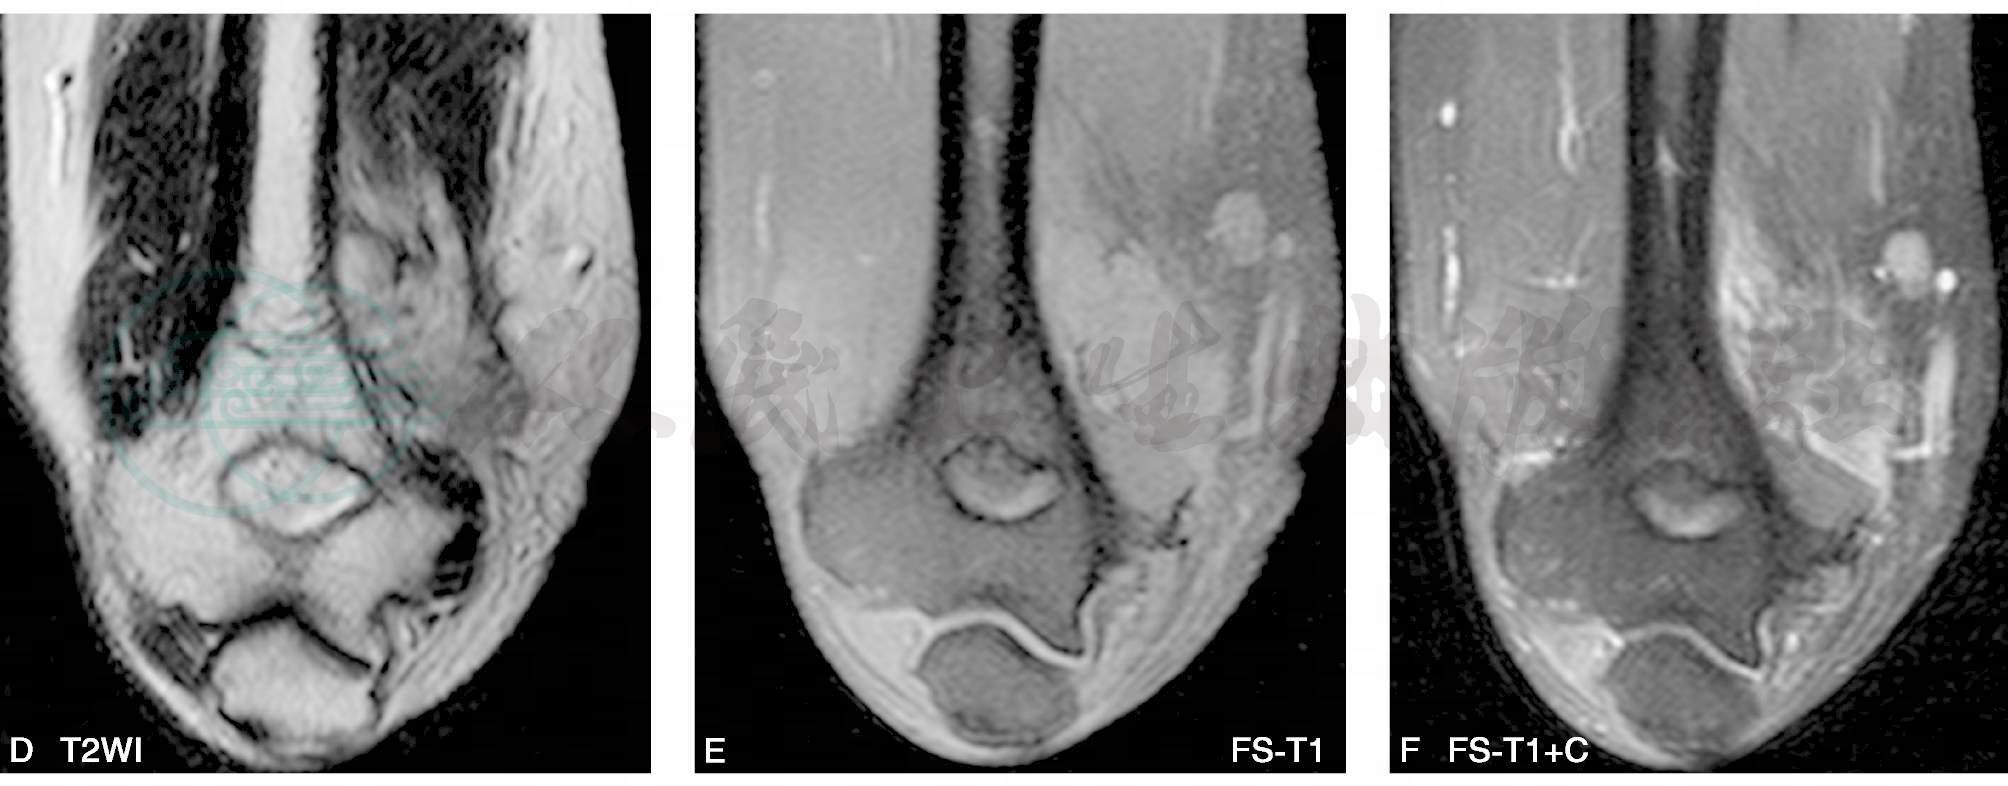

MRI能够直观地显示滑膜肉瘤的病灶形态、范围、与相邻关节、肌腱、滑膜及骨骼的关系。瘤体多表现为不规则,边缘呈分叶状,有时可见较清晰包膜。由于肿瘤常见囊变、出血、坏死以及钙化,因此MR信号不均。肿块内部的信号特点与其病理组织成分密切相关,T1WI上,肿块实体部分与周围肌肉信号相比表现为中等稍高信号,瘤体内的出血灶表现为点片状高信号,坏死或钙化区则表现为更低信号;相应的T2WI上肿块实体部分表现为较高信号,坏死灶信号更高,钙化区表现为低信号,出血灶则信号不一,有时可见液-液平面;滑膜肉瘤较具特征性的MR表现是T2WI抑脂序列中,肿瘤表现为结节状稍高信号,结节呈大小近似的“卵石”状,其间有粗细不等的条状、网格状低信号间隔;增强扫描显示病灶不均一显著强化,病理证实系肿块内部含有丰富血窦。